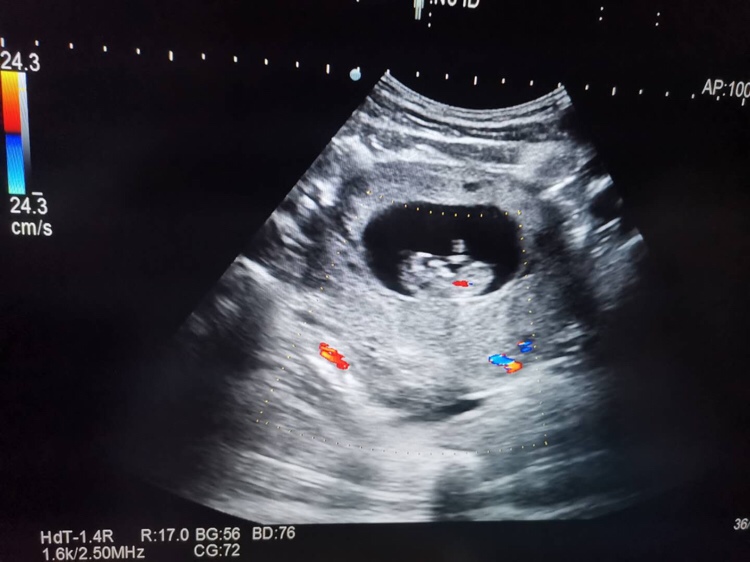

孕12周+5天